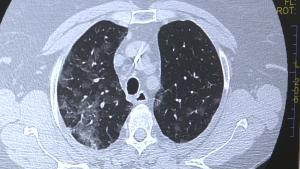

Spitalul de Boli Infecțioase și Pneumoftiziologie „Dr. Victor Babeș Timișoara” a pus la dispoziția pacienților cu patologii pulmonare (fibroză si alte boli interstițiale) dar și medicilor care doresc să obțină…